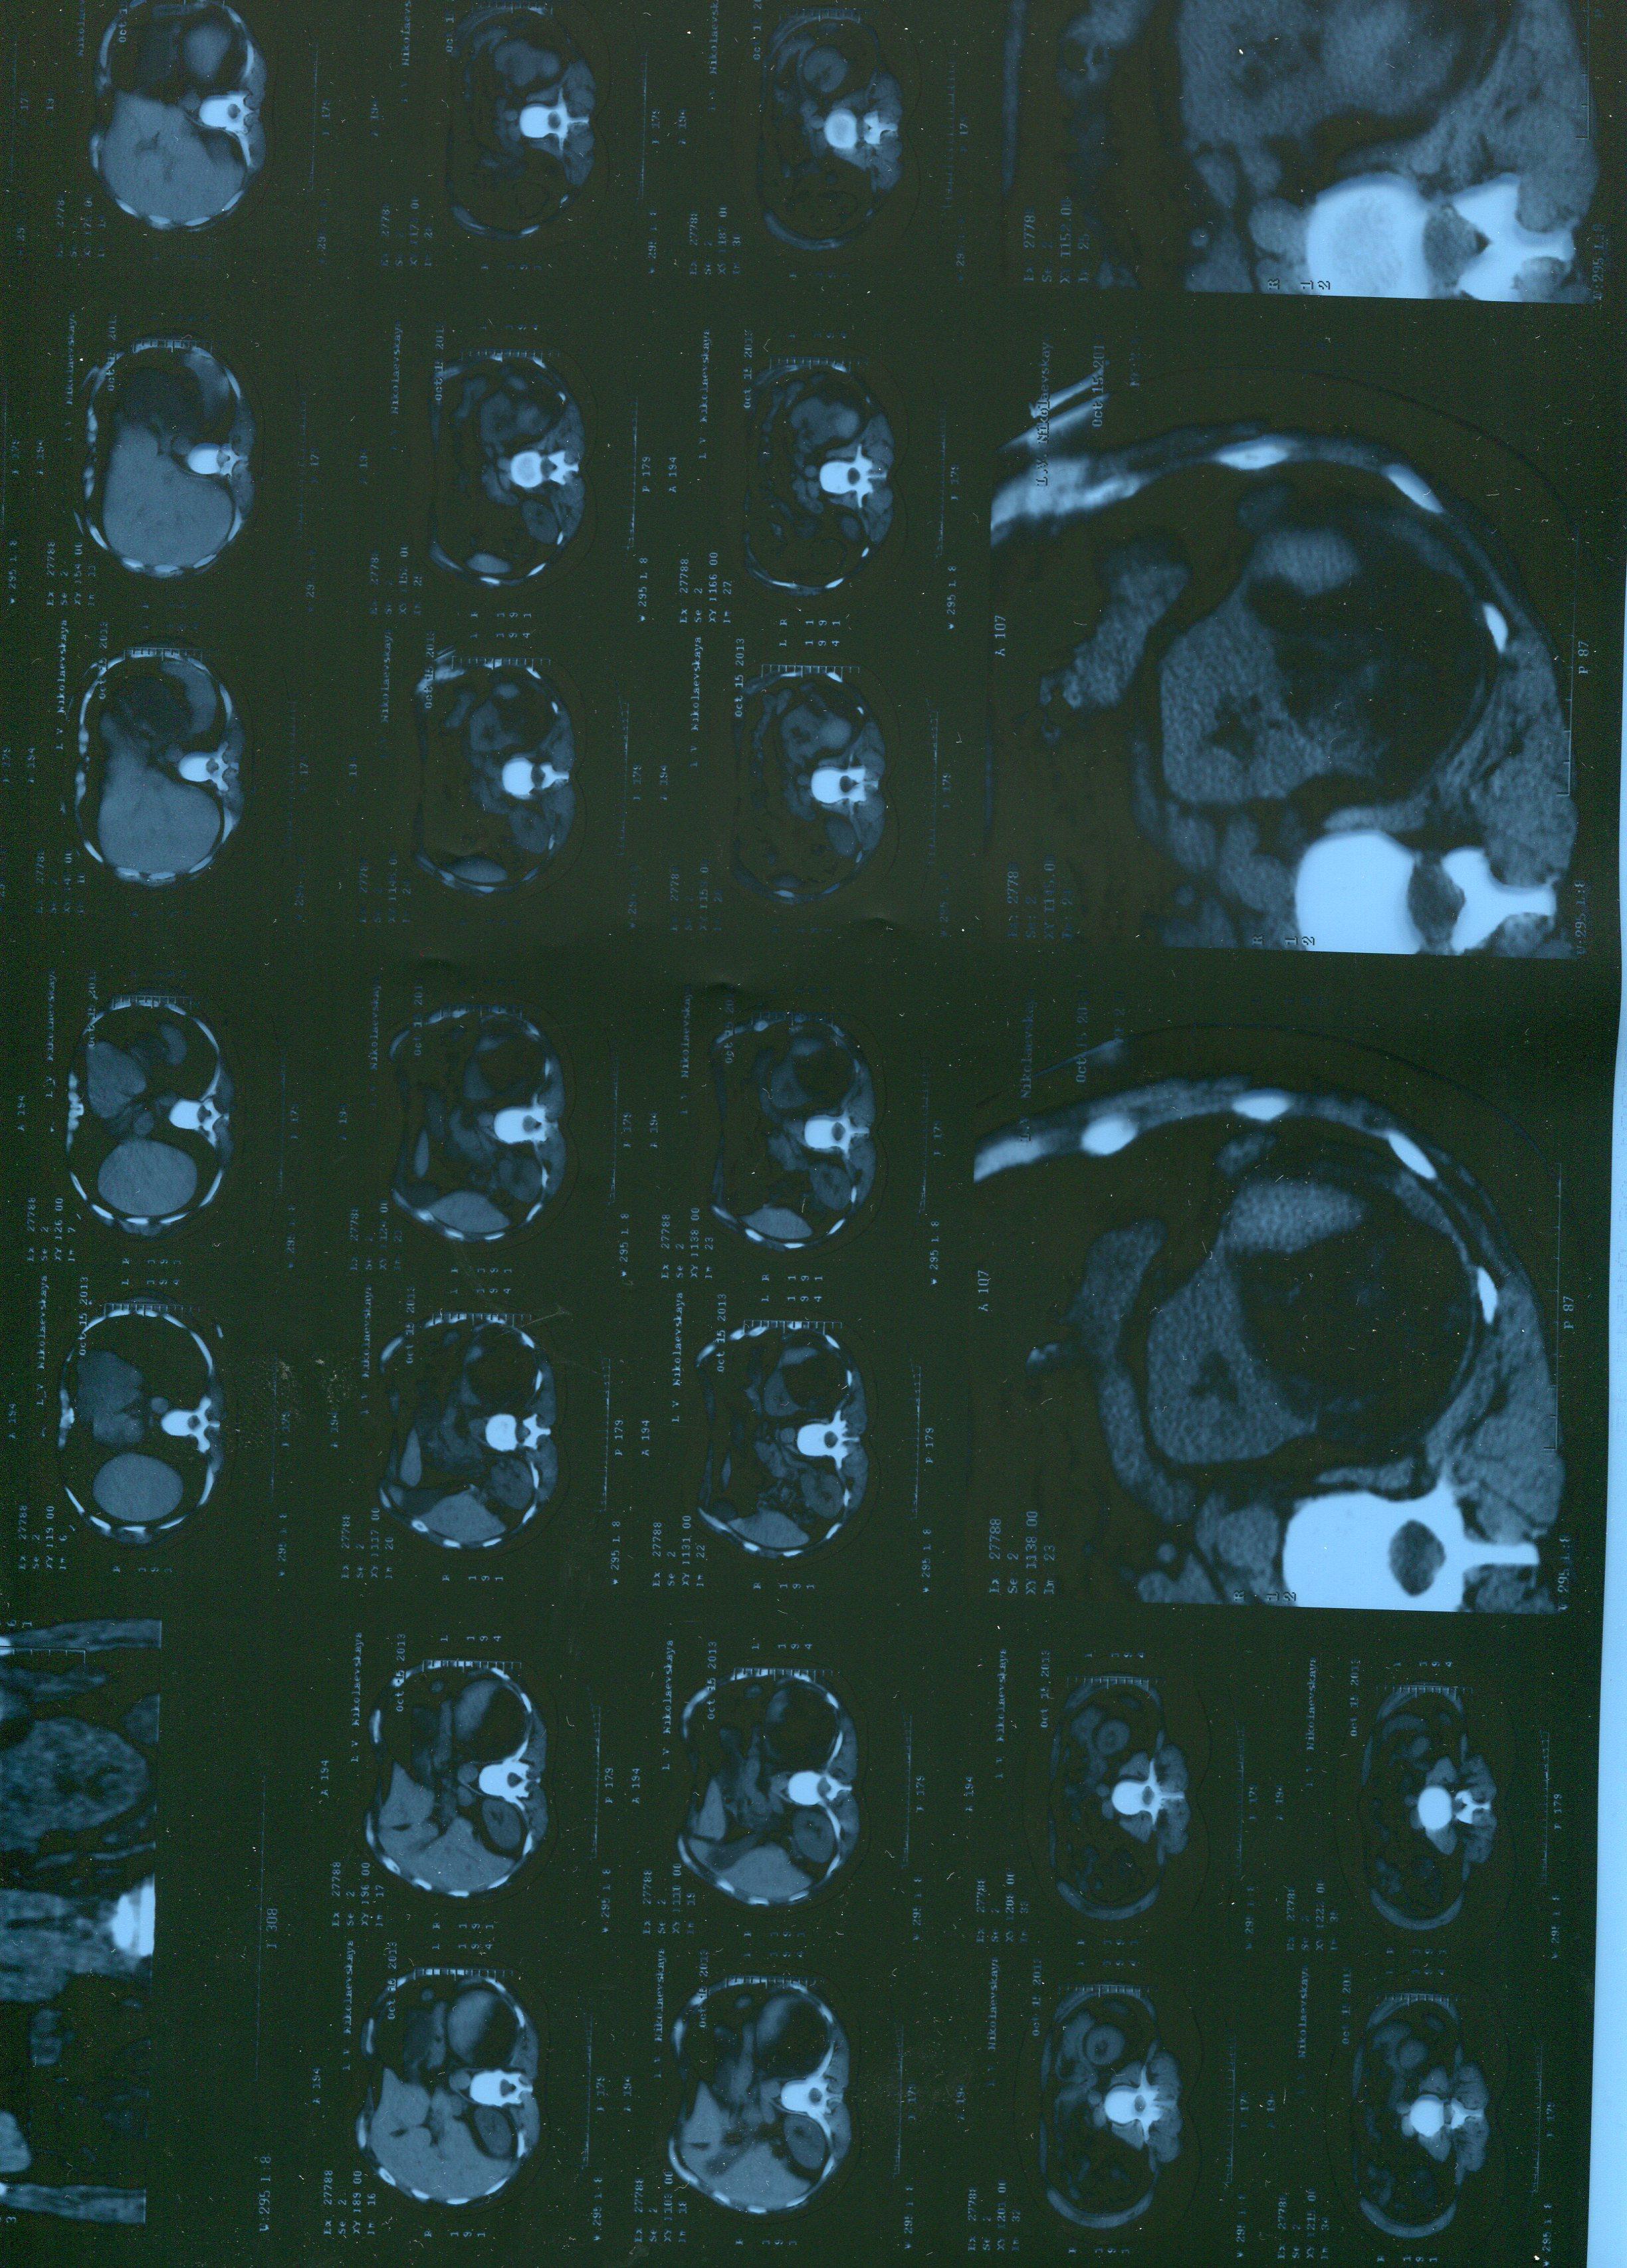

Обычно проводится дополнительное обследование: например, УЗИ. Ваш снимок проводился без дополнительного контрастирования, что затрудняет прямой ответ ан поставленный вопрос. Доверьтесь врачам, вопрос будет решен в период госпитализации, на дооперационном этапе.